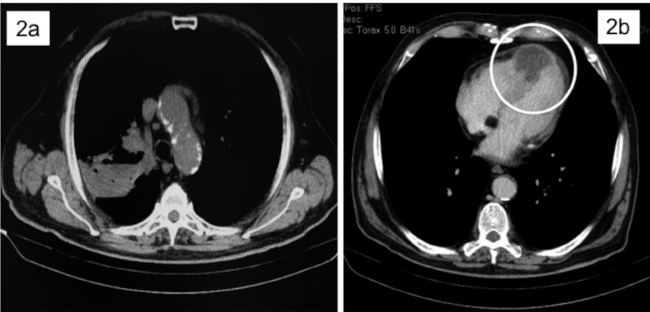

Se trata de un varón de 71 años que acudió al servicio de urgencias con dolor precordial persistente y sensación de falta de aire. Su electrocardiograma mostró supradesnivelación del segmento ST en las derivaciones de V2 a V4 (Figura 1a). Tenía como antecedentes hipertensión arterial y tabaquismo. Con diagnóstico de SCACEST fue trasladado a nuestro centro para angioplastia primaria. En la coronariografía se evidenció una estenosis severa en el segmento distal de la arteria descendente anterior (LAD) que se trató con un stent farmacoactivo (Figuras 1c y 1d). La evolución posterior fue atípica, persistiendo la supradesnivelación del segmento ST pero sin aparición de ondas Q de necrosis (Figura 1b) y sin elevación de troponina. A los 7 días reaparecieron los síntomas (dolor precordial refractario, disnea y ortopnea). La TC detectó un cáncer primario de pulmón en el lóbulo superior derecho, infiltración miocárdica del tabique interventricular (Figura 2) y metástasis óseas y en glándulas suprarrenales. Durante esa hospitalización el patrón ECG fue similar al descrito en el ingreso previo (supradesnivelación segmento ST), probablemente debido a la invasión tumoral del miocardio. Aunque no se realizó biopsia de la masa pulmonar, los hallazgos de la TC indicaron que se trataba de un adenocarcinoma de pulmón. El paciente recibió tratamiento paliativo, falleciendo un mes después de la revascularización coronaria.